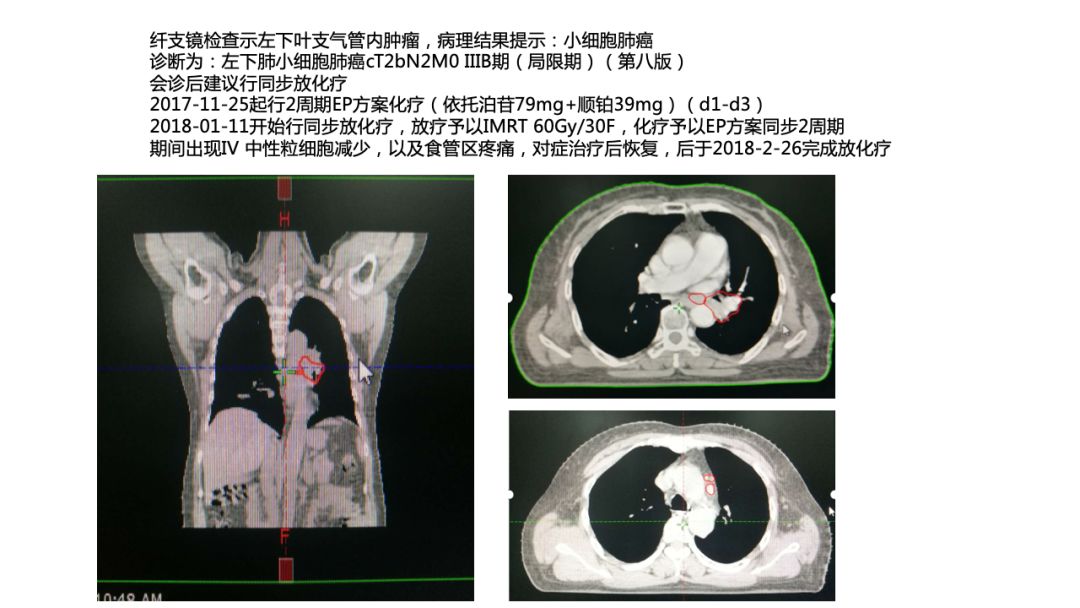

3)纤支镜检查示左下叶支气管内肿瘤,病理结果提示:小细胞肺癌

诊断为:左下肺小细胞肺癌cT2bN2M0 IIIB期(局限期)(第八版)

4)会诊后建议行同步放化疗。

2017-11-25起行2周期EP方案化疗(依托泊苷79mg+顺铂39mg)(d1-d3)。

2018-01-11开始行同步放化疗,放疗予以IMRT 60Gy/30F,化疗予以EP方案同步2周期。

期间出现IV 中性粒细胞减少,以及食管区疼痛,对症治疗后恢复,后于2018-2-26完成放化疗。